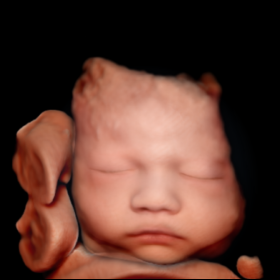

3D/4D визуализация PortraitVue реконструирует реалистичное лицо плода из 3D-данных, создавая естественные черты для диагностики и фото для родителей.